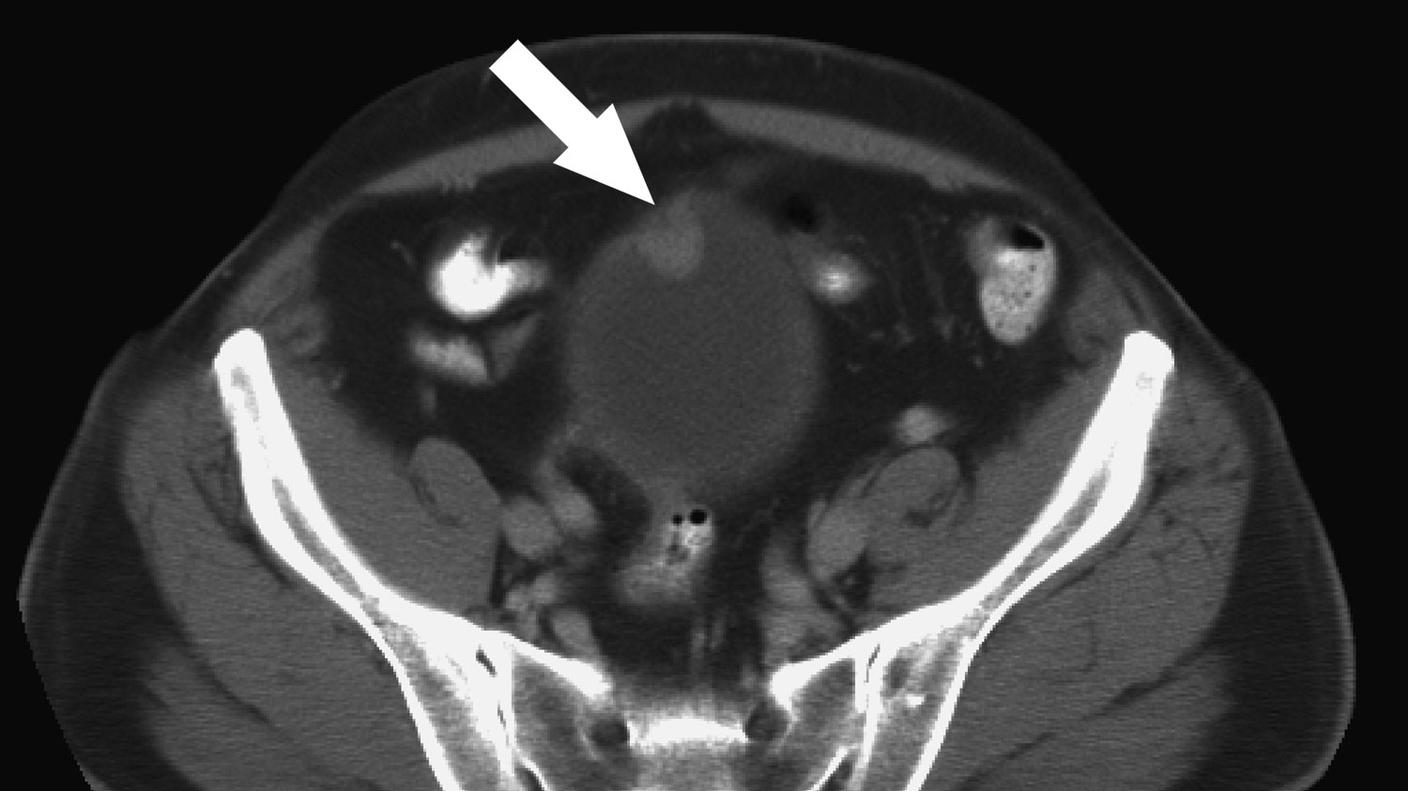

Occupational exposures are a leading risk factor for bladder cancer, second only to smoking. Dr. Koutros is currently leading efforts within large case-control studies of bladder cancer to identify important occupational exposures that might influence risk. Dr. Koutros and her collaborators are examining potential gene-environment interactions as well as incorporating important somatic variation and bladder tumor marker data to integrate exposure, germline genetic variation, and somatic changes to gain insights into the etiology of bladder carcinogenesis.